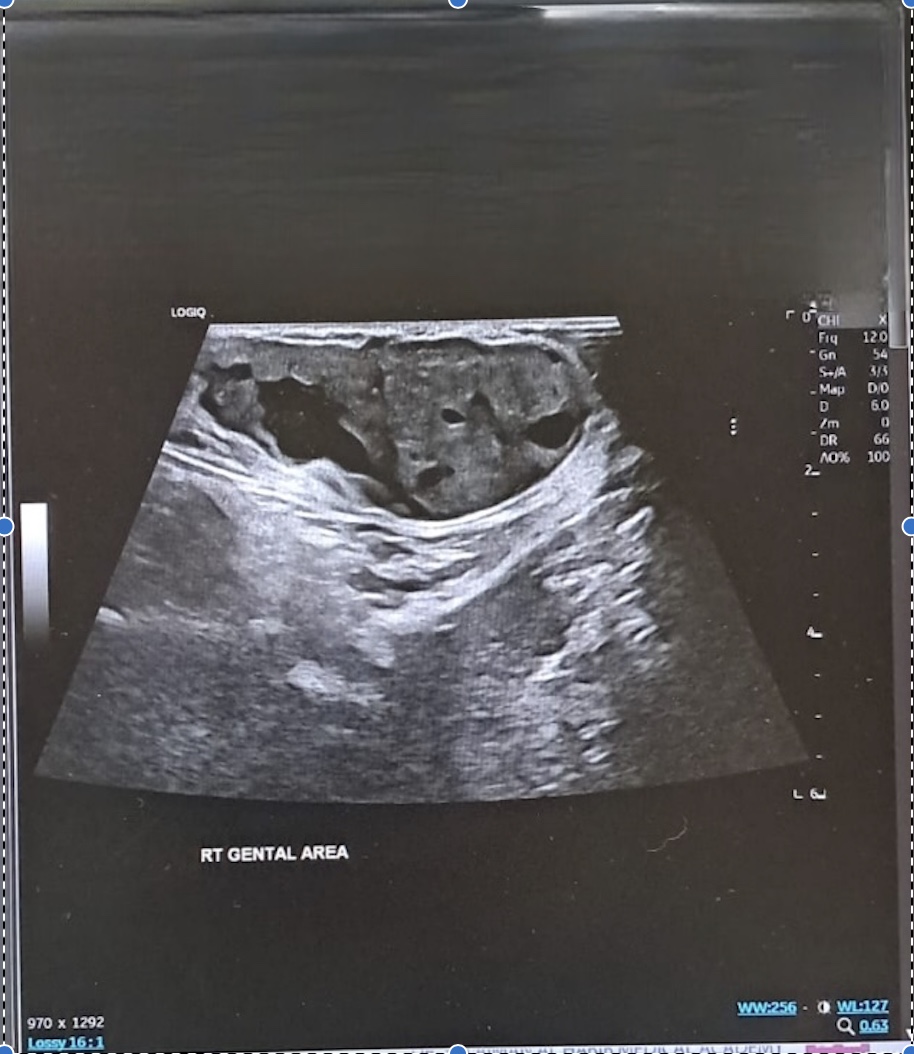

Ultrasound

Numerous medical specialists regard ultrasonography as the most effective modality for the initial imaging of canal of Nuck anomalies. This condition typically presents on ultrasound as a well-defined anechoic lesion exhibiting posterior acoustic amplification, which is characteristic of a hydrocele [3,16]. Figure 2 illustrates the ultrasonographic findings associated with all three types of anomalies. During an ultrasound examination, a lesion may appear hypoechoic or generate low-level echoes due to an elevated protein concentration. In instances where complications arise from a hydrocele, such as infection or hemorrhage, the lesion is likely to exhibit a complicated appearance, characterized by echogenic content, a thickened wall, or internal septations. This is indicative of an increased likelihood of such complications. The presence of a giant cyst may be connected to a smaller cyst with thin walls; both cysts may respond to the pressure applied by the transducer, potentially resulting in a "cyst-in-cyst" appearance, which could lead to misdiagnosis. To differentiate these findings from those of an imprisoned bowel loop, it is essential to utilize Doppler ultrasonography, which can provide clarity regarding the absence of visible color flow within the lesion [16,17].